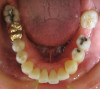

Fig 5. Clear aligner treatment was recommended to this patient, who presented with a missing lower molar combined with

posterior and anterior malocclusion.

Figure 5

Fig 6. Clear aligner treatment was recommended to this patient, who presented with a missing lower molar combined with

Figure 6

Fig 7. Clear aligner treatment was recommended to this patient, who presented with a missing lower molar combined with